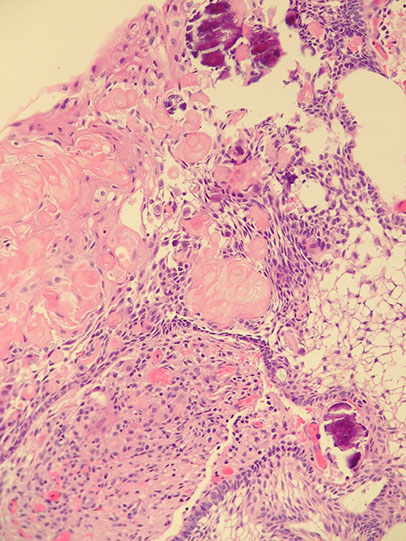

Craniopharyngioma

Rare, Grade I, in sellar region of kiddos, that is slow- growing and can damage hypothalamus and compress optic chiasm, usually near the 3rd ventricle which can impede CSF cycle causing inc pressure in different areas of brain (hydrocephalus)

- derived from epithelial remnants of Rathke pouch

- usually suprasellar

Gross: partly solid (c calcifications and "machine-oil" liquid) and partly cystic components

Histo:

2 distinct microscopic patterns and ages of presentation:

1) Adamantinomatous: tumor of young adults, sellar region, cystic, contains "motor oil" 2/2 proteins in blood and cholesterol crystals)

- ameloblastic-like epithelium (peripheral palisading [squamous nests surrounded by columnar cells], stellate reticulum [loose squamous nests])

- wet keratinization (clumps of anuclear, "ghost" keratinocytes

- dystrophic calcification on CT

- finger-like extension into adjacent brain parenchyma

Genes: mutations in CTNNB1 encoding B-catenin (can be tested for using IHC, which shows accumulation of stain in nuclei)

2) Papillary craniopharyngioma: older pts, more posterior (in 3rd ventricle), non-cystic

- bland squamous prolif c focally papillary architecture (resembles squamous papilloma seen elsewhere in the body)

- no keratinization

- no calcification

- easier to resect and recur less often

- Genes: mutations in BRAF V600E